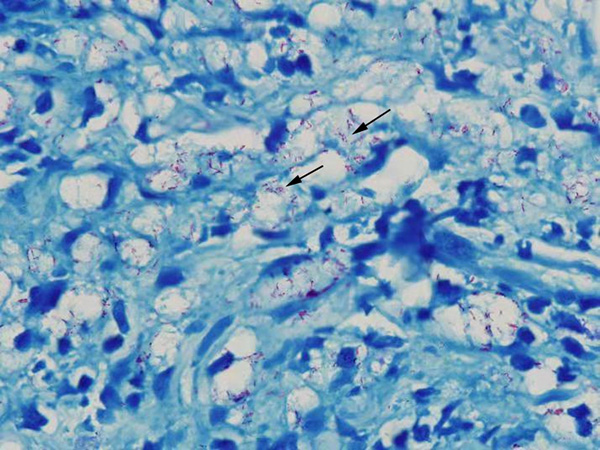

麻风患者皮肤组织病理抗酸染色图片(1000X),图中红色的菌团就是麻风菌

麻风病诊断包括临床检查和实验室检查。临床检查包括检查麻木、斑块、神经粗大等等,实验室检查包括皮肤切刮组织液检查,病理检查,此外还有抗体、T细胞检查和PCR等。抗酸染色后在显微镜下看到完整的红色杆菌是麻风病诊断的金标准。